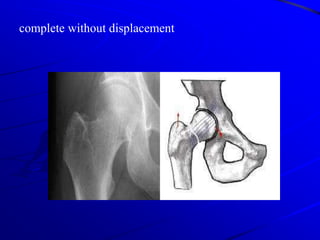

complete without displacement

incomplete fracture of the neck(so called abducted or impacted)